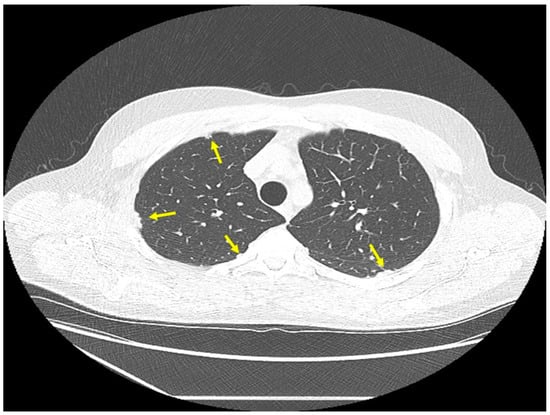

Figure 2.

Chest CT scan image of a patient with pulmonary sarcoidosis, demonstrating lung opacities from granulomatous inflammation around airways (arrows).